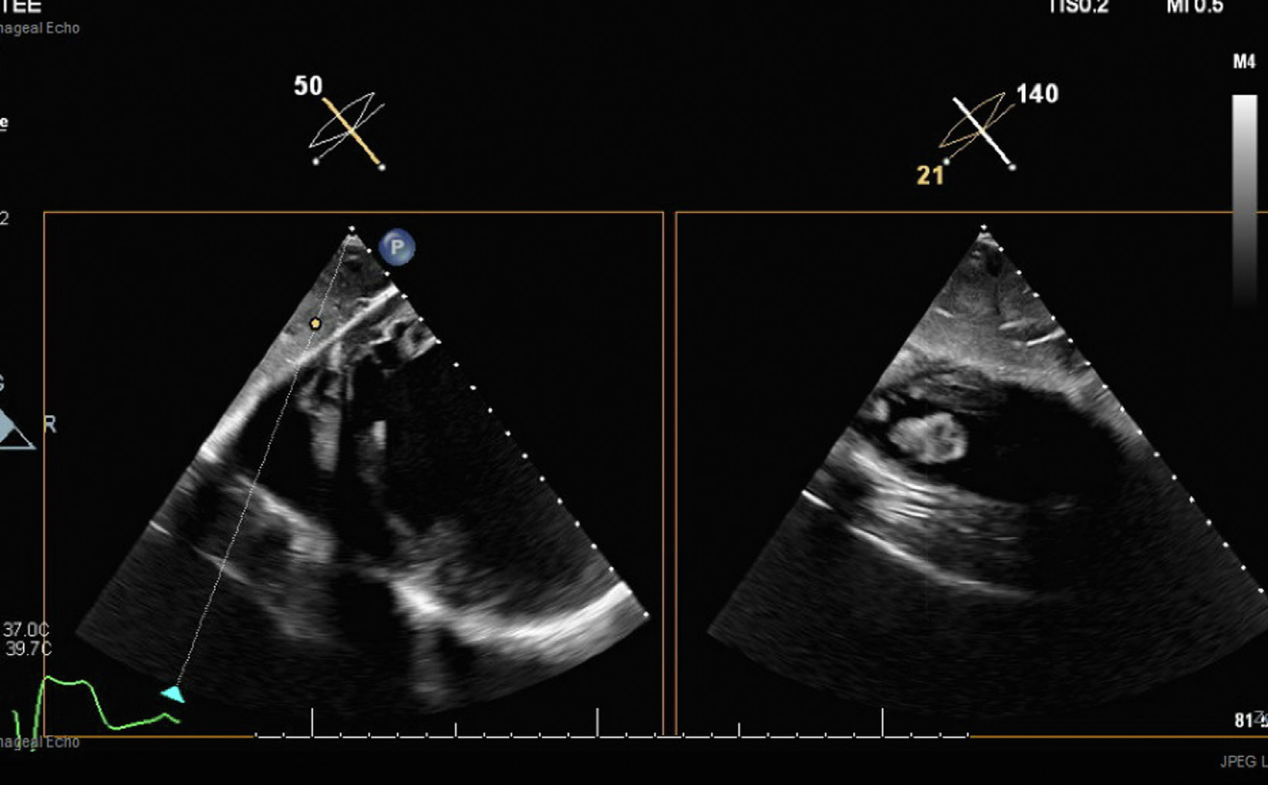

行经胸超声心动图

(TTE)检查显示射血分数(EF)<20%,但较之前相比无变化。未见Fontan梗阻或渗漏证据,且未观察到2个月前显影的心尖部血栓(图1)。双下肢超声未见深静脉血栓形成

图1 经胸超声心动图示:入院前右心室血栓已消退